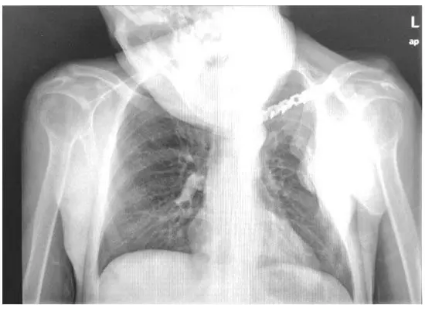

患者,男,年龄44岁,身高173 cm,体质量56 kg。“发现脊柱后凸畸形10余年”,入院诊断:强直性脊柱炎

伴后凸畸形。拟行 “电视镜透视下脊柱后路截骨矫形椎弓根内固定术”。2年前外伤后 “右侧锁骨骨折切开复位内固定术”,术后致头部向右侧斜颈,活动受限(图1)。

图1 患者胸部正位片示,患者因外伤致锁骨骨折,颈部活动度完全受限